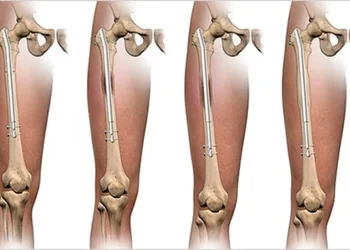

ادامه مطلبجراحی افزایش قد؛ راهکاری علمی برای درمان کوتاهی قابلتوجه قد

به گزارش جام کوردی، محمد اکبری استاد دانشگاه پزشکی ایران و متخصص فیزیوتراپی گفت: در مواردی که طول اندامهای فرد،...